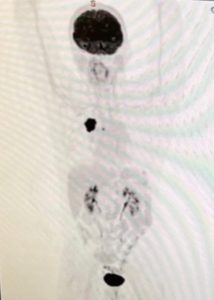

Conquérir le cancer du poumon non à petites cellules (CPNPC) de stade 4

On m’a souvent demandé ce qui me rend si passionné par ce que je fais et par ma vie. 🙏 À vrai dire, tout au long de ma vie et de mes 44 années en tant que praticienne de l’acupuncture, la passion a été « alimentée » par de nombreuses et nombreuses pulsions au sein de mon moi spirituel profond. Certains le savent à mon sujet et d’autres n’en ont aucune idée. Depuis juillet 2020, à peine 3 semaines avant mon 63e anniversaire, un nouveau désir est apparu que je considère désormais comme mon « processus de vie » par opposition au processus de mort ». D’où le nom de ma clinique Acupuncture Bien-être.